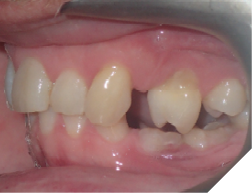

5. Oral hygiene (Fig. 12AB)

Checking for:

i. Bleeding upon probing

ii. Plaque/calculus amount at the gingival of the fixed retainer

iii. Any gingival recession or hyperplastic gingival tissues

Fig. 12A

Fig. 12B